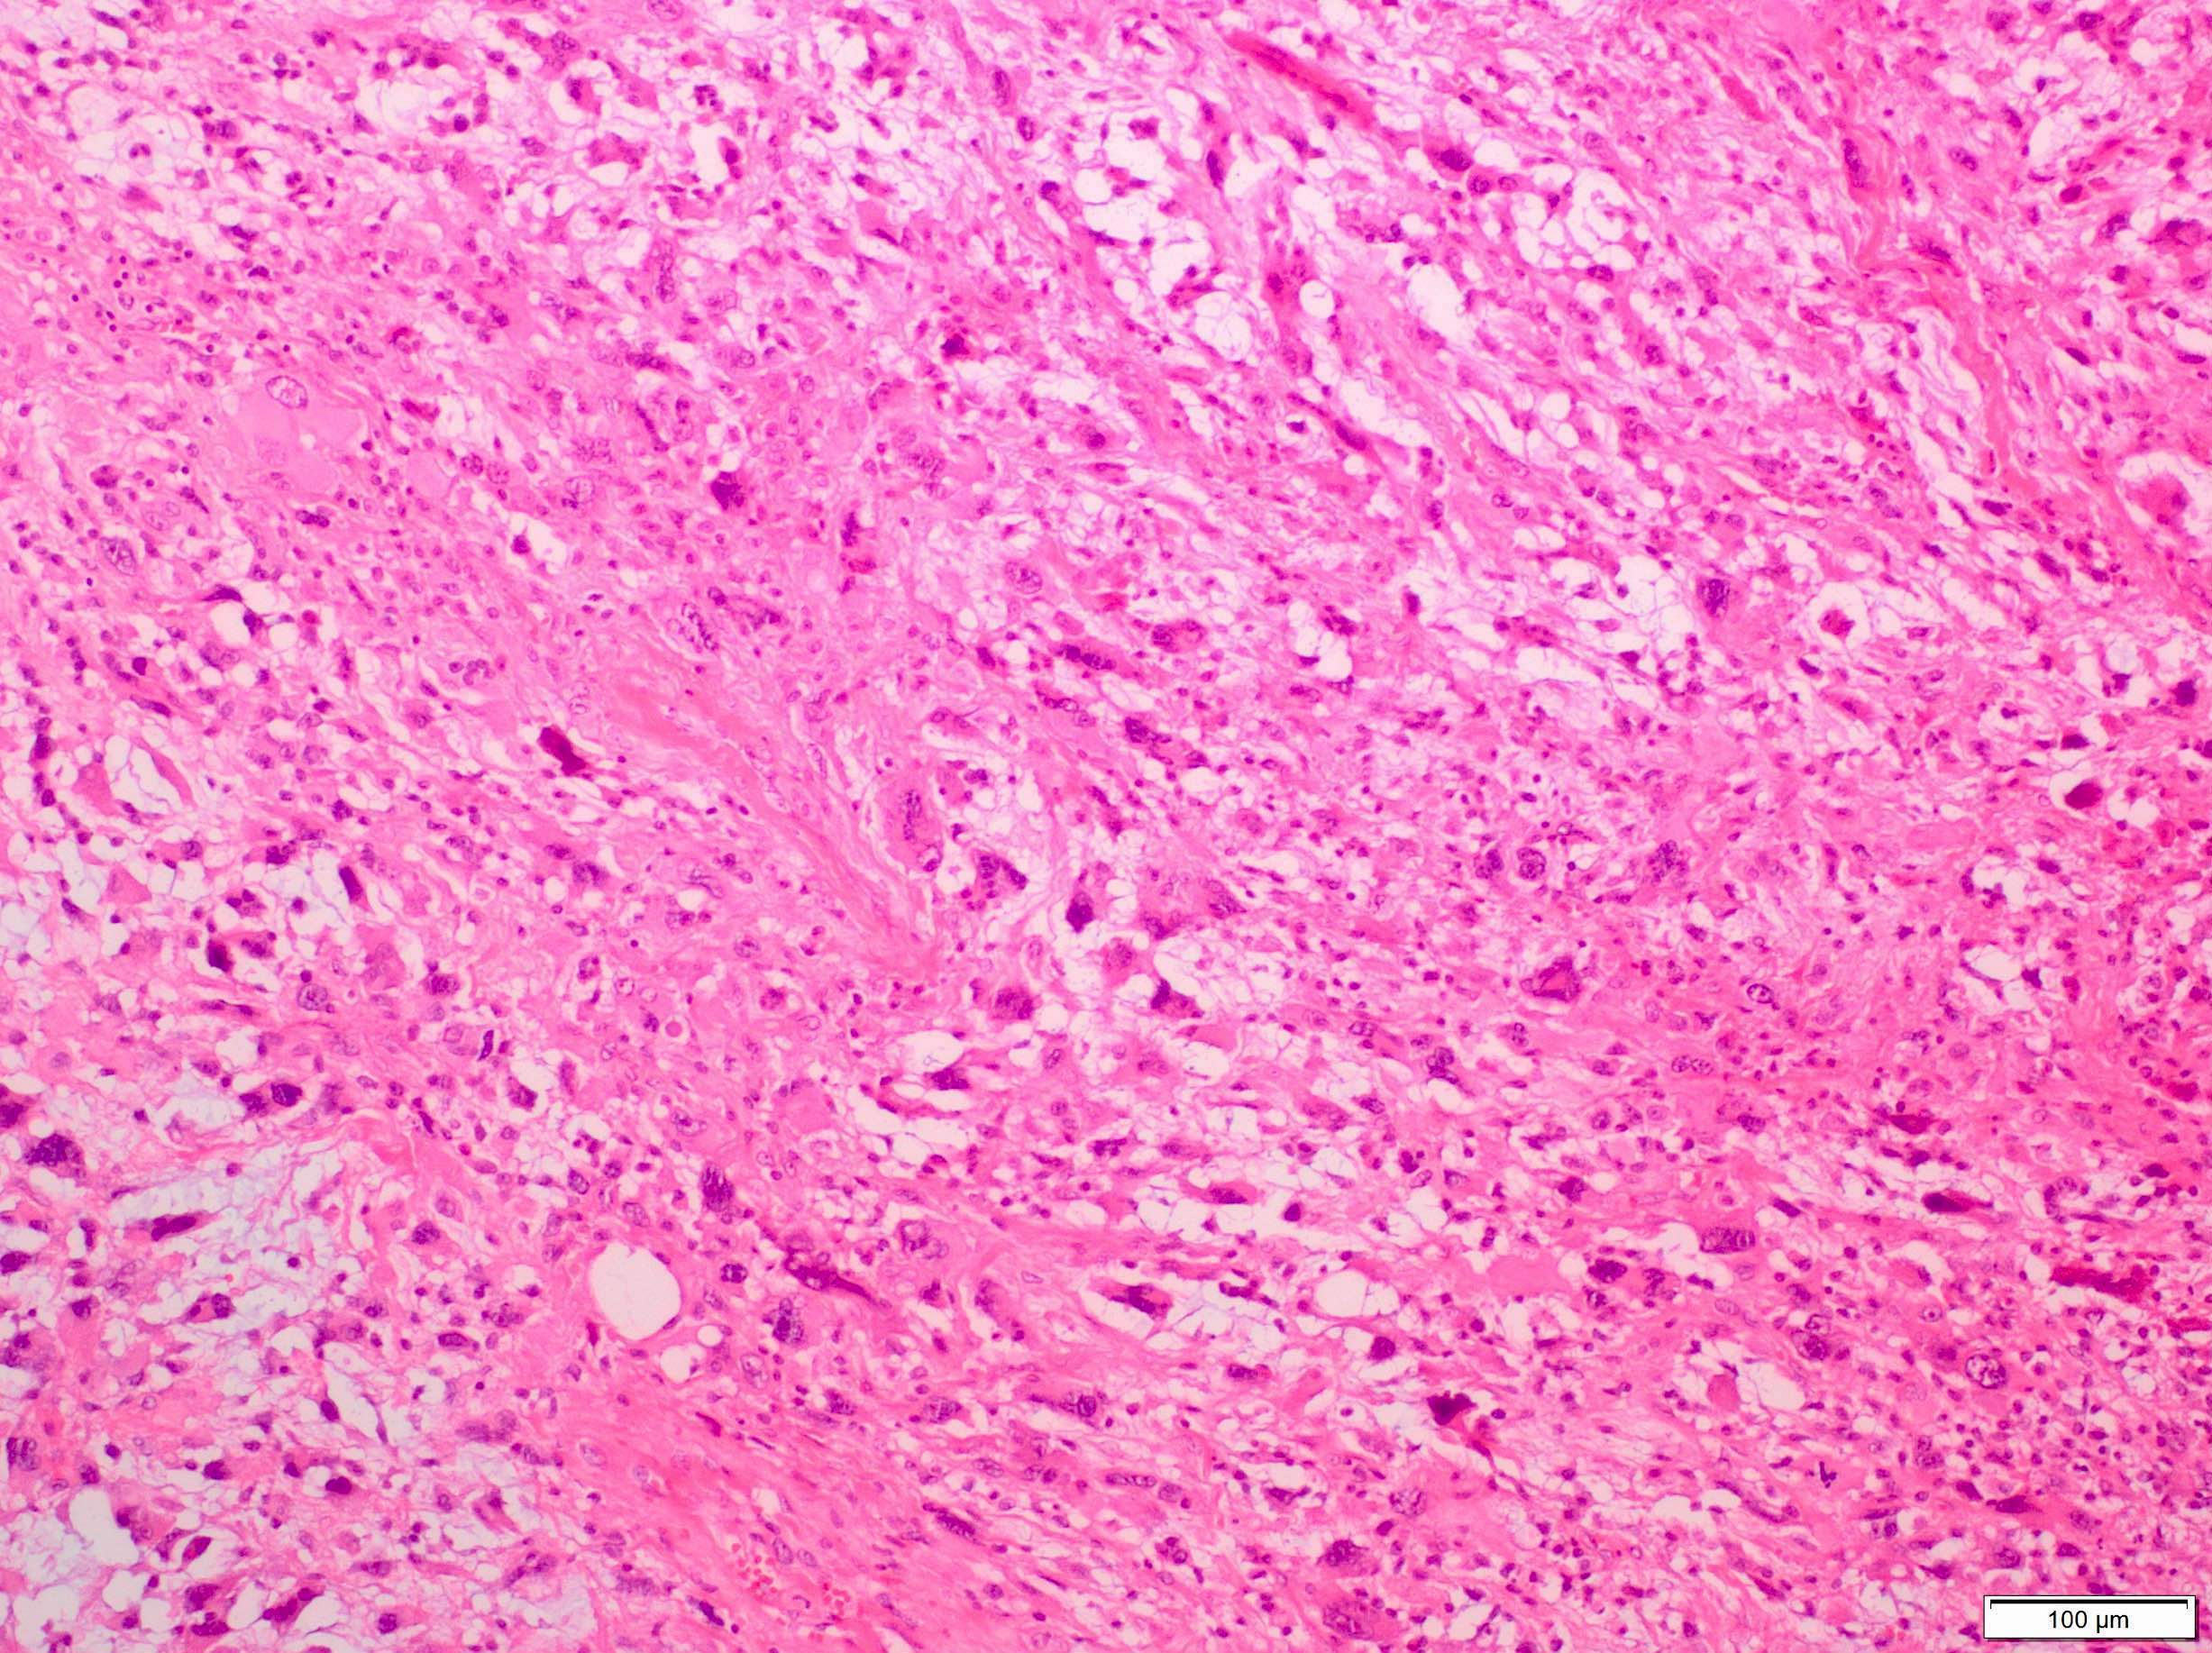

Microscopic (histologic) description

- Sheets of large, atypical and frequently multinucleated polygonal, spindled or rhabdoid eosinophilic cells (Am J Surg Pathol 2009;33:1850)

- Cross striations are seldom detected

Microscopic (histologic) images